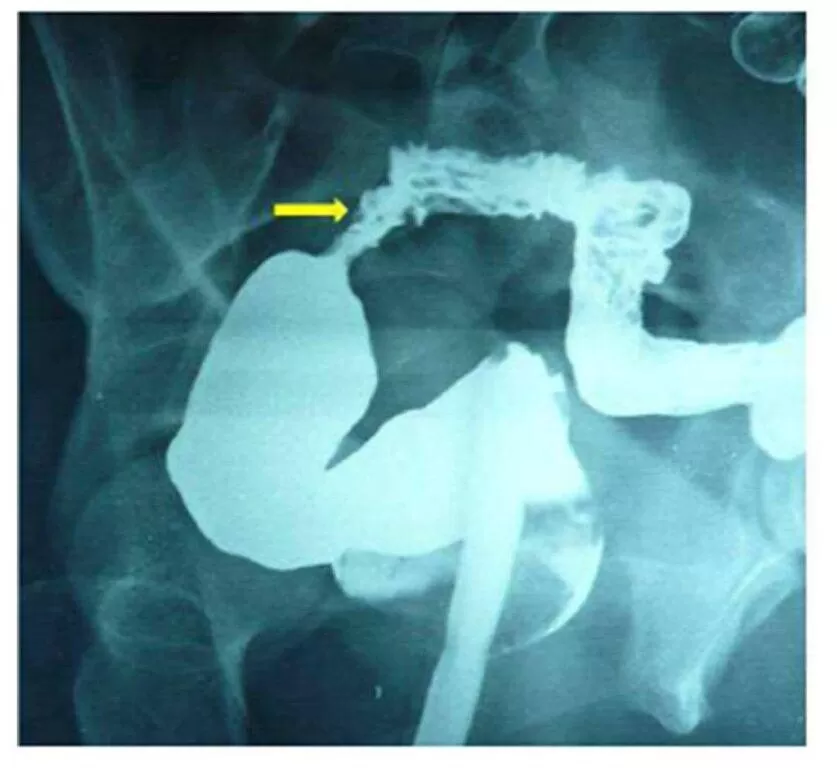

Trans-vaginal sonography (TVS) and Trans-rectal scanning showed a retroverted uterus with a short segment of sigmoid colon adherent to its anterior wall. Uterine myometrium was thinned out at this site with a suspicious track between the uterus and bowel loop suggesting a possibility of utero-sigmoid fistula. Sigmoidoscopy was inconclusive. Hysterosalpingography (HSG) was done with difficulty in passing the cannula, and it revealed contrast-opacified sigmoid colon and adjacent bowel loops. The uterus and the fallopian tubes could not be well appreciated (Fig.1).

Figure 1:  HSG (AP and lateral views) show contrast opacification of sigmoid colon (arrow) and adjacent bowel loop raising suspicion of presence of fistulous communication. Uterus and fallopian tubes could not be appreciated.